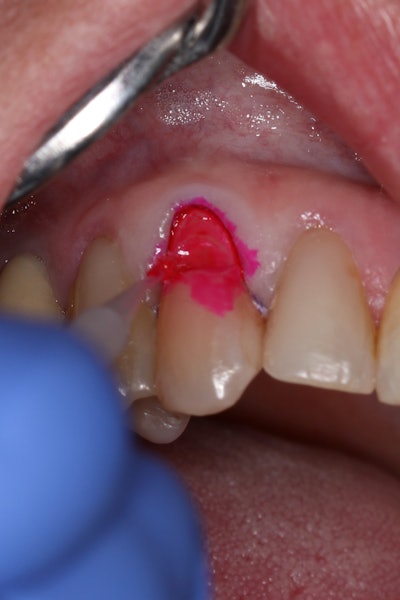

Clearfil Majesty ES Flow in shade UD (Universal Dark) was placed in 0.5-mm increments, with each layer light-cured prior to the next (Figure 7).

Figure 7: Incremental placement of Clearfil Majesty ES Flow in shade UD (Universal Dark) in 0.5-mm layers.Figure 7: Incremental placement of Clearfil Majesty ES Flow in shade UD (Universal Dark) in 0.5-mm layers.

Approximately three to four layers were used to fully restore the lesion to its final contour (Figure 8). The spherical fillers and light-scattering properties of the flowable composite allowed for seamless shade integration with the surrounding enamel.

Figure 8: Completed restoration after full placement of Clearfil Majesty ES Flow in multiple increments.Figure 8: Completed restoration after full placement of Clearfil Majesty ES Flow in multiple increments.Finishing and polishing